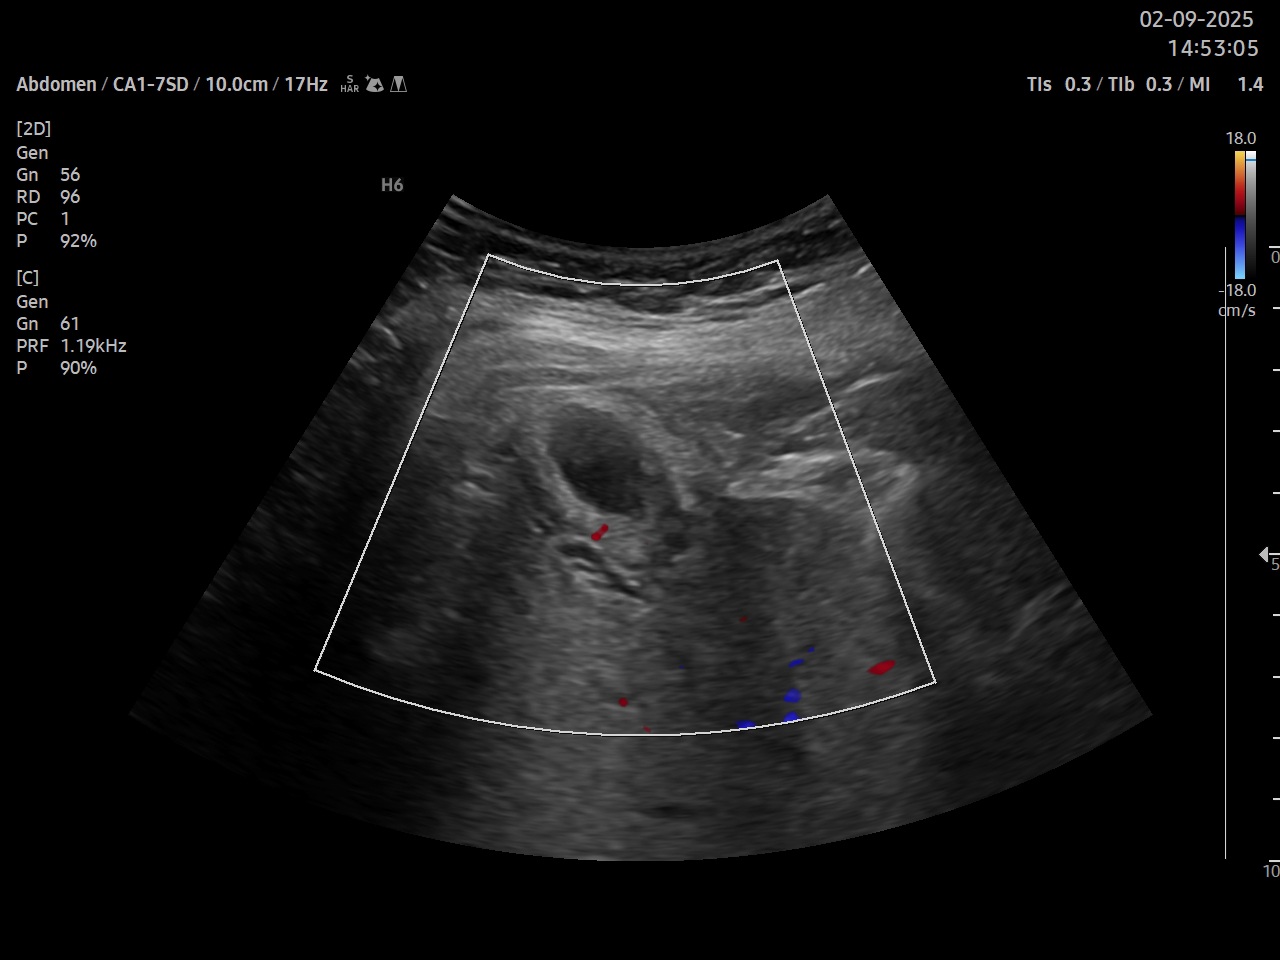

Ecografía clínica: parénquima hepático homogéneo de bordes lisos, signo de Murphy ecográfico positivo, vesícula biliar distendida a pesar de no ayuno con tres imágenes hiperecogénicas con centelleo y sombra posterior, pared engrosada hiperecogénica, se detecta líquido perivesicular. Doppler pulsado a nivel de arteria cística. Páncreas visible en parte sin alteraciones en su interior, no se visualiza Wirsung ni dilatación a nivel de ampolla de Vater, bazo y riñones de tamaño y ecoestructura normal, mioma uterino, vejiga parcialmente replecionada, aorta de calibre normal.

Colelitiasis con signos de Colecistitis

Según los criterios de Tokio 2018, el diagnóstico de colecistitis se establece con la combinación de signos locales de inflamación: dolor en hipocondrio derecho y Murphy positivo, signos sistémicos de inflamación: leucocitosis con neutrofilia, hallazgos de imagen: pared vesicular engrosada (mas de 3 mm), vesícula distendida, presencia de litiasis y Murphy ecográfico positivo, líquido pericístico así como elevación de la velocidad pico sistólica en la arteria cística.